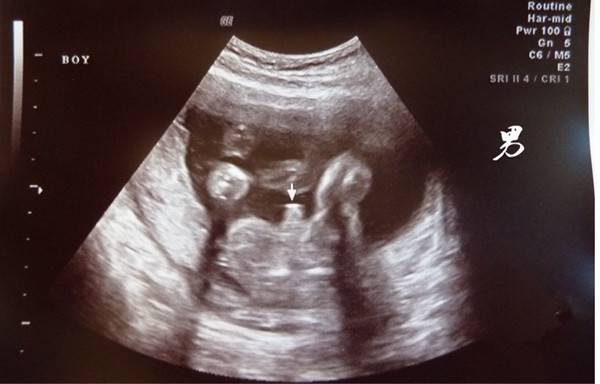

b超有两点基本是男孩,主要指的是孩子的双腿之间生殖器官那里。在做b超的时候如果有幸看到胎儿腿部间有两个或者三个亮点的话,基本怀的就是男孩,如果b超时看到是三条白线,大多数怀的是女孩。

这里的亮点,有宝妈说是男孩的睾丸血流型号,而白线更好区分了,女胎的大小阴唇。除此外,如果胎儿双腿间有一团菌状物体的话基本是男孩,也有的说男孩小JJ像一个小茶壶和小乌龟,男孩的生殖器会凸出来。